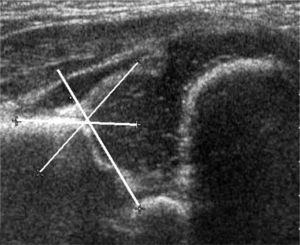

Pocos años más tarde del reporte inicial de Graf, el radiólogo americano Theodore Harcke y sus colaboradores publicaron su experiencia con una nueva técnica de exploración. Ellos reconocieron en su artículo el gran potencial diagnóstico revelado previamente por Graf, pero consideraron su técnica como compleja respecto del equipamiento y del entrenamiento necesario para obtener imágenes satisfactorias (26, 27). La nueva técnica que ellos propusieron corresponde a una exploración dinámica de la cadera, obteniendo dos planos standard de evaluación, uno coronal y otro trasversal, sin y con maniobras dinámicas, equivalentes a las de Ortolani y Barlow. (figura 10) Harcke clasificó las caderas como estables, cuando no presentan cambios con las maniobras dinámicas; inestables, cuando existe una pequeña separación de la cabeza con respecto al fondo de acetábuo o cuando la cabeza se luxa lateralmente pero vuelve a su posición concéntrica durante el examen; y dislocada, cuando la cabeza está situada permanentemente lateral a la línea de base. Morfológicamente, la cadera estable de Harcke es equivalente al tipo I de Graf; la cadera inestable tiene su símil en el tipo IIc; y la cadera dislocada abarcaría el espectro de los tipos IId, III y IV de Graf. Las mediciones han sido consideradas como opcionales en esta técnica. (28-30).